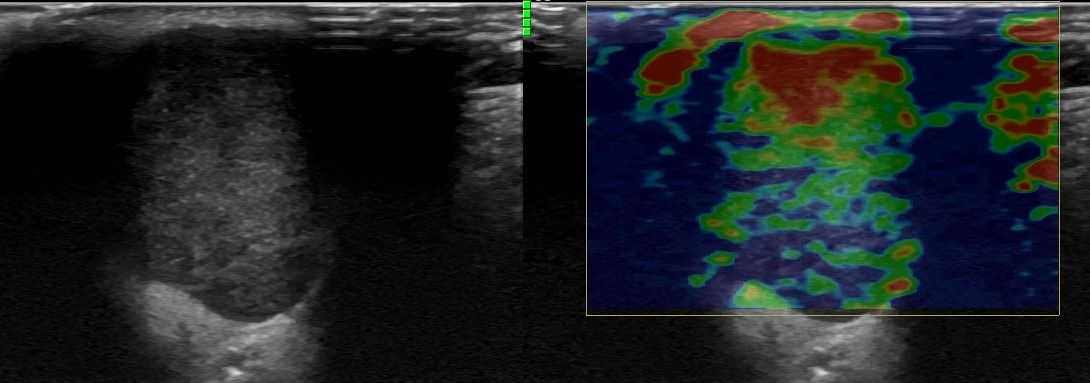

Το υψηλής ευκρίνειας Έγχρωμο Υπερηχογράφημα Σιελογόνων Αδένων με την τεχνική της Ελαστογραφικής Μελέτης μπορεί να διαγνώσει αξιόπιστα παθολογίες όπως;

- Εστιακές βλάβες, όπως όγκοι (πλειόμορφο αδένωμα, όγκος Warthin, λέμφωμα)

Η αξιοπιστία του Υπερηχογραφήματος στη διάγνωση παθολογίας των Σιελογόνων Αδένων έχει καθιερωθεί τα τελευταία χρόνια και εξασφαλίζεται με τη χρήση Υπερηχογράφων τελευταίας γενιάς με ειδικούς υψίσυχνους ηχοβολείς και με την εξοικείωση και εμπειρία του εξεταστή-ιατρού με την ηχοανατομία και παθολογία των Σιελογόνων Αδένων και της περιοχής κεφαλής – τραχήλου.